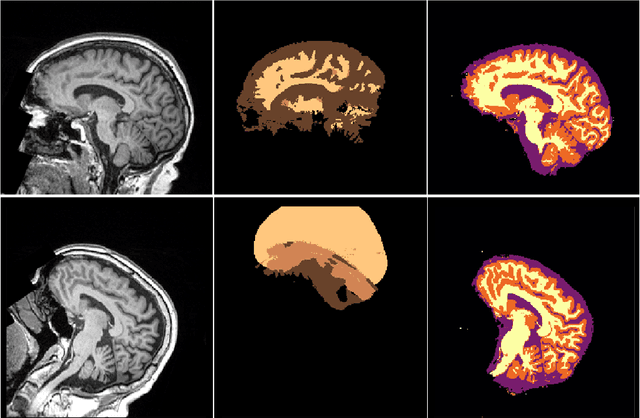

Abstract:NeuroNet is a deep convolutional neural network mimicking multiple popular and state-of-the-art brain segmentation tools including FSL, SPM, and MALPEM. The network is trained on 5,000 T1-weighted brain MRI scans from the UK Biobank Imaging Study that have been automatically segmented into brain tissue and cortical and sub-cortical structures using the standard neuroimaging pipelines. Training a single model from these complementary and partially overlapping label maps yields a new powerful "all-in-one", multi-output segmentation tool. The processing time for a single subject is reduced by an order of magnitude compared to running each individual software package. We demonstrate very good reproducibility of the original outputs while increasing robustness to variations in the input data. We believe NeuroNet could be an important tool in large-scale population imaging studies and serve as a new standard in neuroscience by reducing the risk of introducing bias when choosing a specific software package.